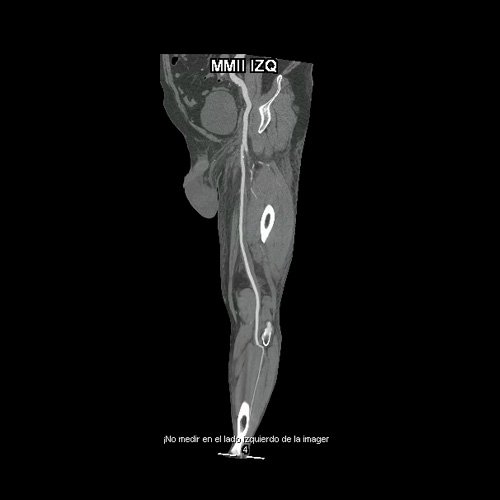

• AngioTAC de miembros inferiores (Día 0): Ateromatosis parietal calcificada parcheada en todo el territorio aorto-ilíaco-femoral bilateral. LADO DERECHO: Arteria ilíaca interna: de calibre y trayecto conservado, permeable. Arterias ilíaca externa y femoral común: de calibre y trayecto conservados, permeables. Arterias circunfleja ilíaca superficial y epigástrica superficial: de calibre y trayecto conservados, permeables. Arteria femoral superficial: de calibre y trayecto conservado, permeable. Arteria femoral profunda: de calibre y trayecto conservado, permeable. Arterias circunflejas femoral medial y lateral: de calibre y trayecto conservados, permeables. Arteria poplítea: de calibre y trayecto conservado, permeable. Arteria tibial anterior: de calibre y trayecto conservado, permeable. Arteria tibial posterior: de calibre y trayecto conservado, permeable. Cambios artrodegenerativos coxo-femorales y tricompartimentales en la rodilla. Signos de entesopatía cuadricipital distal. No se observan alteraciones a nivel de los grupos musculares visualizados. La disposición del tejido graso es normal. LADO IZQUIERDO: En fase angiográfica se observa menor calibre y opacificación de las arterias femoral superficial y profunda, poplítea y de sus ramas musculares en muslo y pierna en comparación con el miembro contralateral, con opacificación arterial preservada. En fase venosa se evidencia mayor la densidad endovascular de las mismas hasta el tercio distal de la pierna, donde se logran identificar a las arterias peronea, tibial anterior y tibial posterior. Se evidencia un defecto de relleno de la vena ilíaca común izquierda, en su nacimiento, en relación a trombosis venosa profunda. No se identifica compromiso de la porción visualizada de la vena cava inferior ni del sistema venoso ilíaco contralateral. Se visualiza aumento del tamaño de todos los grupos musculares del muslo izquierdo con respecto al contralateral y retardo de la concentración de contraste, asociado a edema de los tejidos blandos superficiales. Reticulación de la grasa de la región inguinal. Cambios artrodegenerativos coxo-femorales y tricompartimentales en la rodilla. Signos de entesopatía cuadricipital distal. No se observan alteraciones a nivel del fémur ni de las porciones visualizadas de la tibia y el peroné.

• AngioTAC de miembros inferiores (Día 2): Ateromatosis parietal calcificada parcheada en todo el territorio aorto-ilíaco-femoral bilateral. LADO DERECHO: Arteria ilíaca interna: de calibre y trayecto conservado, permeable. Arterias ilíaca externa y femoral común: de calibre y trayecto conservados, permeables. Arterias circunfleja ilíaca superficial y epigástrica superficial: de calibre y trayecto conservados, permeables. Arteria femoral superficial: de calibre y trayecto conservado, permeable. Arteria femoral profunda: de calibre y trayecto conservado, permeable. Arterias circunflejas femoral medial y lateral: de calibre y trayecto conservados, permeables. Arteria poplítea: de calibre y trayecto conservado, permeable. Arteria tibial anterior: de calibre y trayecto conservado, permeable. Arteria tibial posterior: de calibre y trayecto conservado, permeable. Vena ilíaca primitiva: 13 mm, vena ilíaca externa 11 mm, vena ilíaca interna 7 mm. LADO IZQUIERDO: En esta ocasión, en fase angiográfica se observa de calibre y opacificación conservada de las arterias femoral superficial y profunda, poplítea y de sus ramas musculares en muslo y pierna. En fase venosa se evidencia un defecto de relleno endoluminal de la vena primitiva izquierda que impresiona extenderse actualmente a la vena iliaca externa, a la vena femoral superficial y poplítea, hasta nivel del hueco homonimo, las cuales se visualizan aumentadas de calibre con respecto a sus contralaterales, en relación a trombosis venosa profunda. Se sugiere cotejar con ecodoppler de miembros inferiores. No se identifica compromiso de la porción visualizada de la vena cava inferior ni del sistema venoso ilíaco contralateral. Se visualiza dispositivo vascular en VCI (filtro VCI), infrayacente a las venas renales. Presenta aumento del diámetro del muslo izquierdo con respecto a su contralateral, asociado a edema de los tejidos blandos superficiales. Reticulación de la grasa de la región inguinal a predominio izquierdo con algunas burbujas aéreas. Se observa inmediatamente infrayacente a los antes mencionado, un área hiperdensa que realza en fase venosa, con centro hipodenso, que mide 2.2 cm x 1.4 cm, ya visualizado en tomografía previa. Cambios artrodegenerativos coxo-femorales y tricompartimentales en la rodilla. Signos de entesopatía cuadricipital distal. No se observan alteraciones a nivel del fémur ni de las porciones visualizadas de la tibia y el peroné. Arteria ilíaca interna: de calibre y trayecto conservado, permeable. Arterias ilíaca externa y femoral común: de calibre y trayecto conservados, permeables. Arterias circunfleja ilíaca superficial y epigástrica superficial: de calibre y trayecto conservados, permeables. Arteria femoral superficial: de calibre y trayecto conservado, permeable. Arteria femoral profunda: de calibre y trayecto conservado, permeable. Arterias circunflejas femoral medial y lateral: de calibre y trayecto conservados, permeables. Arteria poplítea, tibial anterior y tibial posterior: de calibre disminuido con respecto a su contralateral, permeables. Vena ilíaca primitiva: 14 mm, vena ilíaca externa 17 mm, vena ilíaca interna 9 mm. Calcificaciones en conducto inguinal bilateral. Hidrocele bilateral.

Angio TAC de miembros inferiores (Día 0)